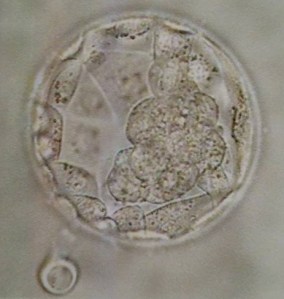

This morning we watched our embryo get placed back into its home.  It is now in the blastocyst stage.  Our little embryo is even starting to hatch!  Before I started this journey, I did not realize that humans do

hatch!  This has to happen in order for it to implant into the uterus lining. In two weeks, we will get blood work done.  This will help us if our embryo has survived.

This is an actual picture of our embryo!  This picture was taken today; before it was transferred back! It is starting to hatch as you can see on the left side of the picture.